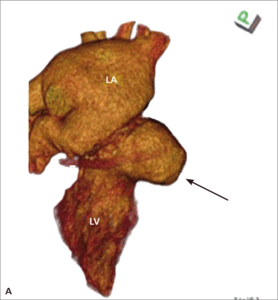

Rycina 1. TEE 3D. Wynik przezskórnego zamknięcia przecieku okołozastawkowego przy protezie uchylno-dyskowej.

Przecieki okołozastawkowe (paravalvular leak, PVL) występują u chorych po implantacji sztucznej zastawki serca, zarówno chirurgicznej, jak i metodą przezskórną lub przezkoniuszkową. W przypadku chirurgicznie implantowanych zastawek są one powikłaniem infekcyjnego zapalenia wsierdzia lub skutkiem poluzowania lub wyprucia fragmentu szwu chirurgicznego albo konsekwencją znacznych zmian typu włóknistego i kalcyfikacji w natywnym pierścieniu zastawkowym, utrudniających prawidłowy kontakt między nim a pierścieniem sztucznej zastawki. Częstość występowania wszystkich (w tym również niewielkich) PVL ocenianych w przezprzełykowym badaniu echokardiograficznym szacuje się na kilkanaście procent u osób po implantacji zastawki aortalnej (aortic valve replacement, AVR) i nieco ponad 20% po implantacji zastawki w pozycji mitralnej (mitral valve replacement, MVR) [1-3]. Według piśmiennictwa kliniczne objawy przecieku okołozastawkowego (niewydolność serca, hemoliza i zwiększone ryzyko wystąpienia infekcyjnego zapalenia wsierdzia) występują u około 1-5% pacjentów po AVR lub MVR [4], przy czym częściej jawne klinicznie są przecieki okołomitralne [5]. Wśród pacjentów z PVL i hemolizą wewnątrznaczyniową należy rozróżnić tych, u których rozpad erytrocytów jest na tyle nasilony, że doprowadza do klinicznie jawnej niedokrwistości, oraz takich, u których przy granicznie małych liczbie czerwonych krwinek i stężeniu hemoglobiny hemolizę wykazać można istotnie zwiększonymi aktywnością LDH, stężeniem bilirubiny pośredniej i haptoglobiny lub zwiększoną liczbą retikulocytów. Diagnostyka obrazowa przecieków okołozastawkowych została szczegółowo omówiona w innych artykułach [6,7]. Leczenie chirurgiczne jest leczeniem z wyboru przy jednoczesnej dysfunkcji zastawki, planowanym jednoczasowym CABG, niestabilności protezy oraz infekcyjnym zapaleniu wsierdzia. W jednej z większych analiz [8] porównujących chorych z PVL leczonych zachowawczo i chirurgicznie wyraźnie udokumentowano korzyść z leczenia zabiegowego (zmniejszenie śmiertelności całkowitej w badanej populacji z 26 do 12%). Alternatywą leczenia chirurgicznego jest przezskórna implantacja zatyczki do kanału przecieku [9]. Wykorzystuje się w tym celu urządzenia dedykowane do zamykania innego typu przecieków wewnątrzsercowych i nieprawidłowych połączeń naczyniowych, jak okludery do zaopatrywania ubytków przegrody międzykomorowej (ventricular septal defect, VSD) czy przetrwałego przewodu tętniczego (patent ductus arteriosus, PDA) lub korki naczyniowe typu Amplatzer vascular plug (AVP, St. Jude Medical). W ośrodku autorów najczęściej wykorzystuje się podczas tych zabiegów korki naczyniowe typu AVP III. Charakteryzują się one spłaszczonym kształtem, co ułatwia ich dopasowanie do zwykle szczelinowatego kształtu przecieku okołozastawkowego. W przypadku przecieków okołomitralnych, szczególnie dostępnych od strony lewego przedsionka lub o znacznych rozmiarach, korzystne może być dojście od strony koniuszka lewej komory serca [10]. Często w zabiegach tych wykorzystuje się więcej niż jedną zatyczkę (ryc. 1).